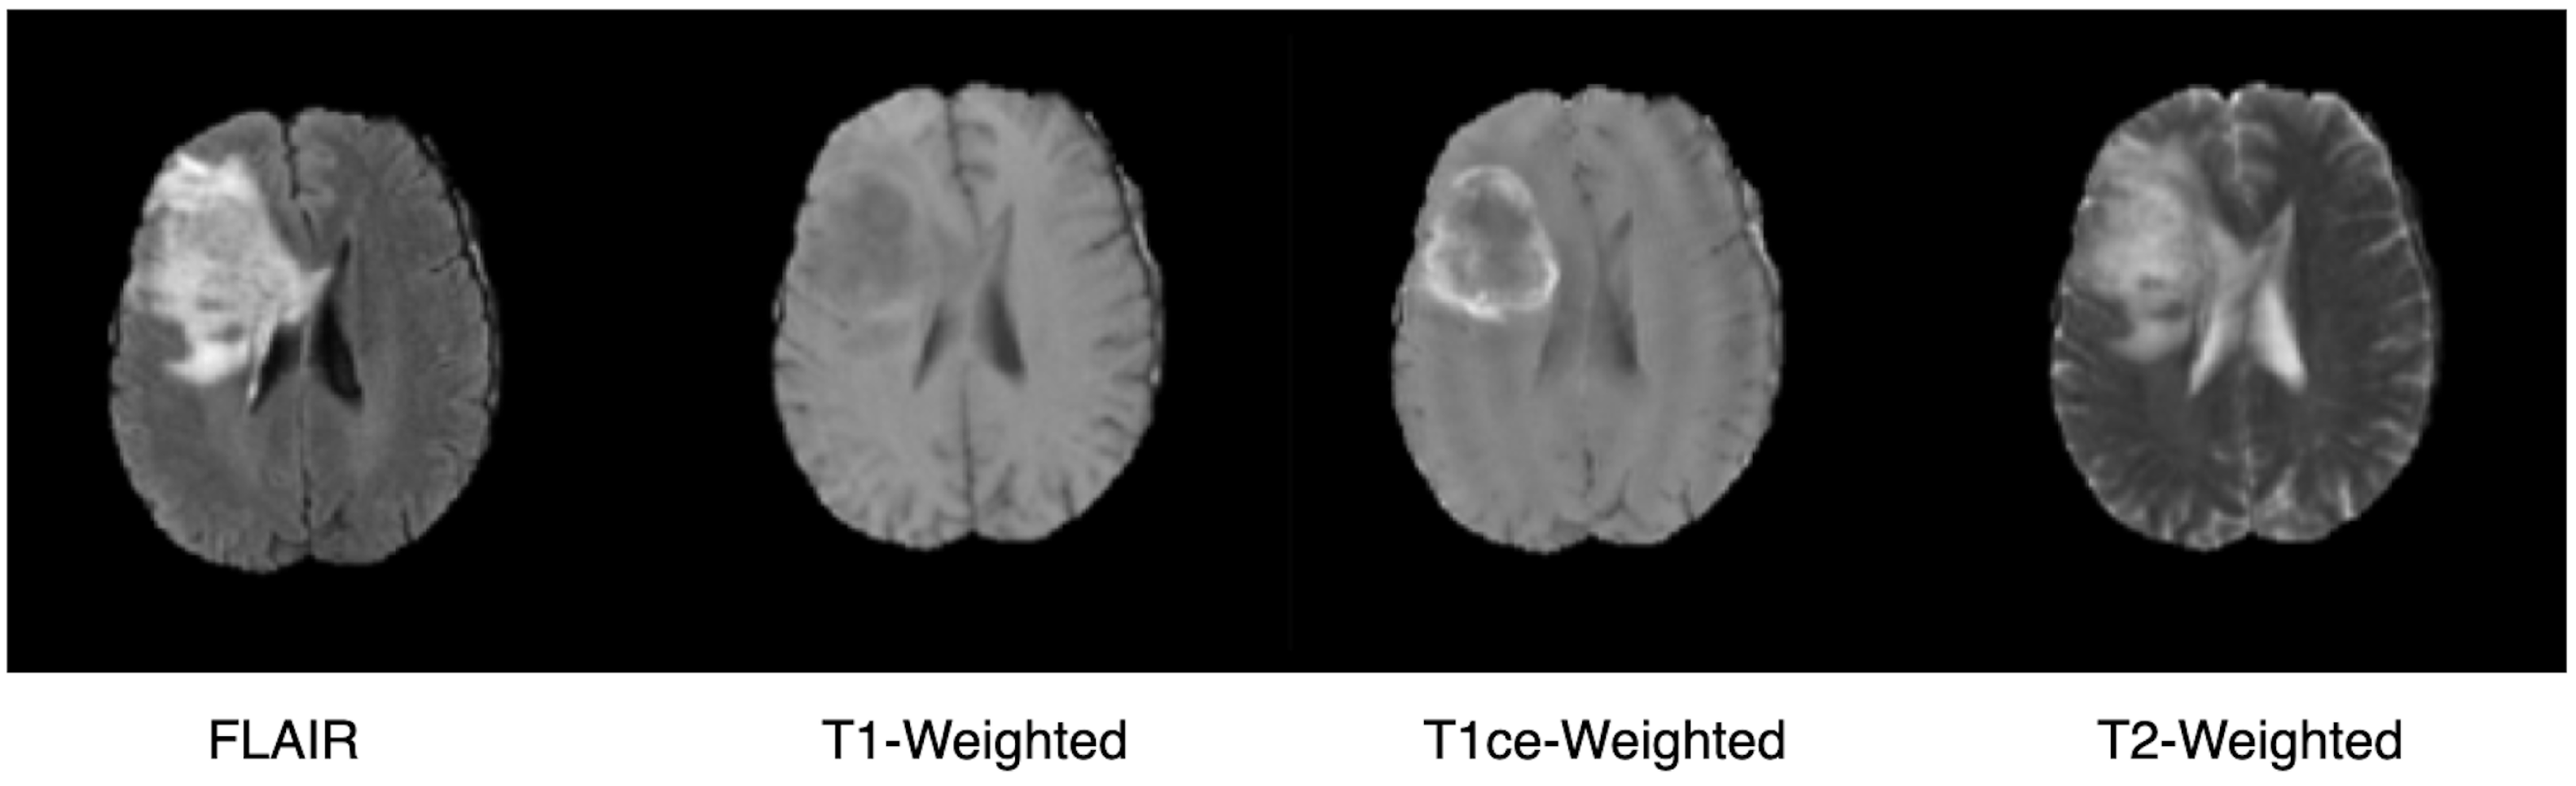

3.2. Dataset

3.3. Segmentation